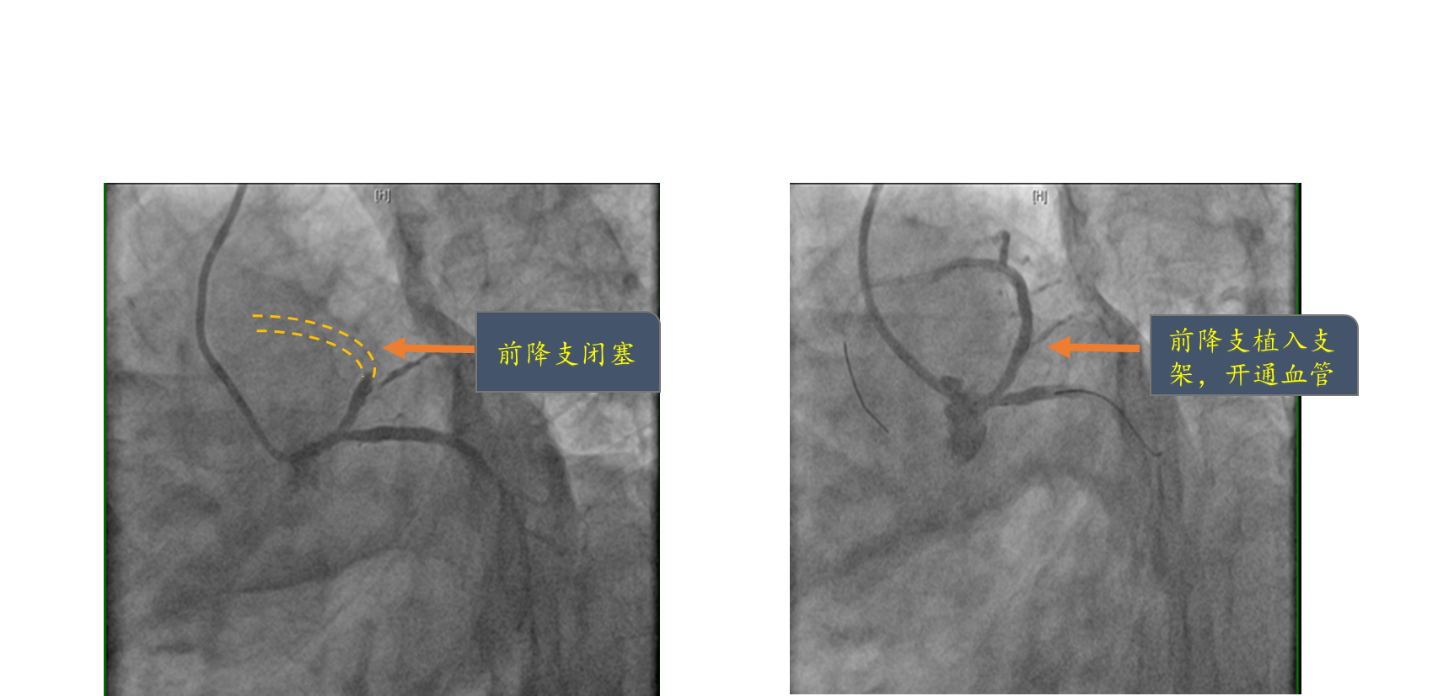

清华长庚医院9月30日电通讯员(薛亚军 周杰)2016年9月14日的下午,居住在立水桥附近56岁的苏先生,活动时突然出现胸部疼痛,就像一块大石头压在胸口那样,让人喘不过气来。没有任何耽搁,苏先生立即叫家人将自己送到东小口社区卫生服务中心。卫生服务中心内科部祝立侠主任及在岗急诊医生,经验非常丰富,接诊后立即行多导联心电图检查,结果提示苏先生有明确急性心肌梗死,即胸前导联ST段呈弓背样抬高,伴T波高尖(如图1),立即呼叫120救护车,将苏先生第一时间送至北京清华长庚医院急诊部,同时通知长庚医院心脏内科介入团队医生。几乎是与时间赛跑,从患者胸痛症状出现,通过东小口社区卫生服务中心经由救护车转运至北京清华长庚医院,长庚医院急诊绿色通道直接接入到心脏导管室,心脏内科介入团队迅速完成冠状动脉造影,很快送入导丝,完成球囊扩张,开通闭塞血管,随后植入支架,整个过程,仅仅50余分钟,成功挽救了患者的生命。术中可见患者供应心脏最主要的左前降支冠脉血管100%闭塞(如图2左),使用球囊扩张开通闭塞血管,放置了一枚支架,永久性的开放闭塞血管(如图2右)。术后,苏先生被转运到心脏重症监护病房(CCU),6天后由CCU转至普通病房继续治疗。14天后苏先生完成心肌梗死后康复训练,恢复正常的日常生活运动,顺利出院。

图1 左图显示前降支近段完全闭塞;右图显示植入支架后,前降支血流恢复正常